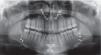

In the panoramic radiograph it was observed that all the teeth were permanent, with absence of the upper and lower left third molars, asymmetric condyles as well as the maxillary sinuses without infectious occupation and continuous alveolar processes without any intraosseous pathology (Figure 2).